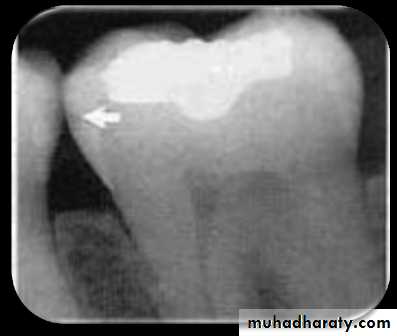

Caries found between two teeth is termed interproximal caries. On a dental image, interproximal caries is typically seen at or just below (apical to) the contact point. This area is difficult, if not impossible, to examine clinically with an explorer. As the caries progresses inward through the enamel of the tooth, it assumes a triangular configuration; the apex (or point) of the triangle is seen at the dentino-enamel junction (DEJ).

As the caries reaches the DEJ, it spreads laterally and continues into dentin. Another triangular configuration is seen in dentin; this time the base of the triangle is along the DEJ, and the apex is pointed toward the pulp chamber

Proximal caries classified according to its severity

Incipient inter proximal caries extends less than half way through the thickness of enamelModerate inter proximal caries extends more than half way through enamel

Advanced inter proximal caries extends to or through the dentanoenamel junction and into dentin but does not extend through the dentin more than half the distance toward the pulp (affects both enamel and dentin(Severe inter proximal caries extends through enamel and through dentin more than half distance toward the pulp (involve both enamel and dentin(